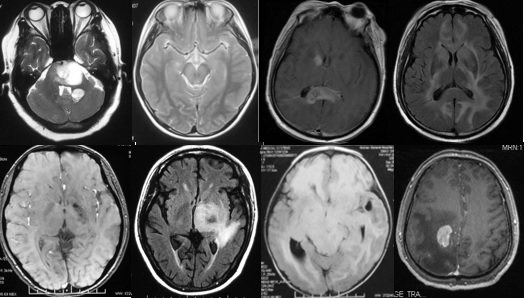

重要申明:以下每个部分会配磁共振图片,因疾病和影像之间存在同病异象、同像异病,为避免误导,图片不标注疾病,请各自鉴赏,另其中有部分图片来源于网络,有疑问可与本人联系。

T--toxication,中毒/trauma,外伤。

个人认为这里的中毒理解为毒物相关的病变更合理一些。

如酒精中毒相关的,如MBD。

各种中毒,有机溶剂,如苯、甲醇、一氧化碳中毒、氨己烯酸中毒等。

*品毒**如*洛因海**、*卡因可**等。

抗肿瘤或免疫*制剂抑**如甲硝唑、5-FU(5-氟尿嘧啶)及其前体药物卡培他滨、他克莫司、甲氨蝶呤、贝伐单抗等相关性脑病。

S--stroke,卒中,即血管性

各种动脉性、静脉性血管病、静脉窦血栓形成、动脉夹层致脑梗塞、脑小血管病、脑动静脉畸形、CAA等,Moya-Moya也可出现脑实质的多发病灶,易被误诊为脱髓鞘。